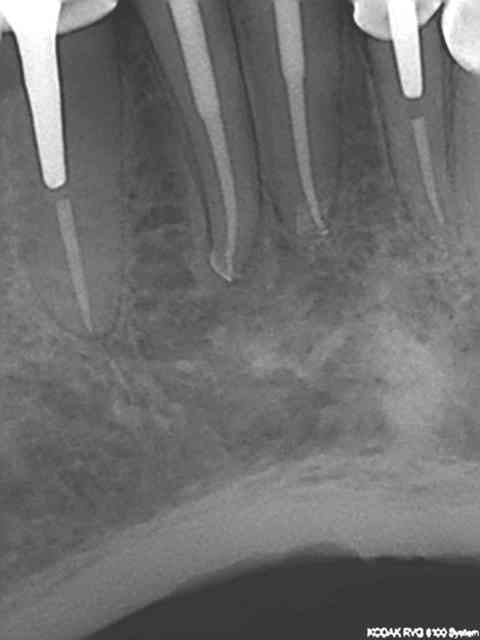

Regardez les endo de chicot29, mono cone et postez vos endo thermo et on compare !

Et effectivement un cone en 6 % n'a rien à voir avec un cone en 2%. L'efficacité tu la vois avec le temps, et un bon mono-cone scellé à l'apex donne des résultats plus que corrects. Je thermo-compacte au machtou quand je fais l'empreinte dans la séance de l'endo)))))

R1 c2o32p - Eugenol

R2 b6cnxj - Eugenol

R3 qrzatb - Eugenol

R4 dqlzan - Eugenol